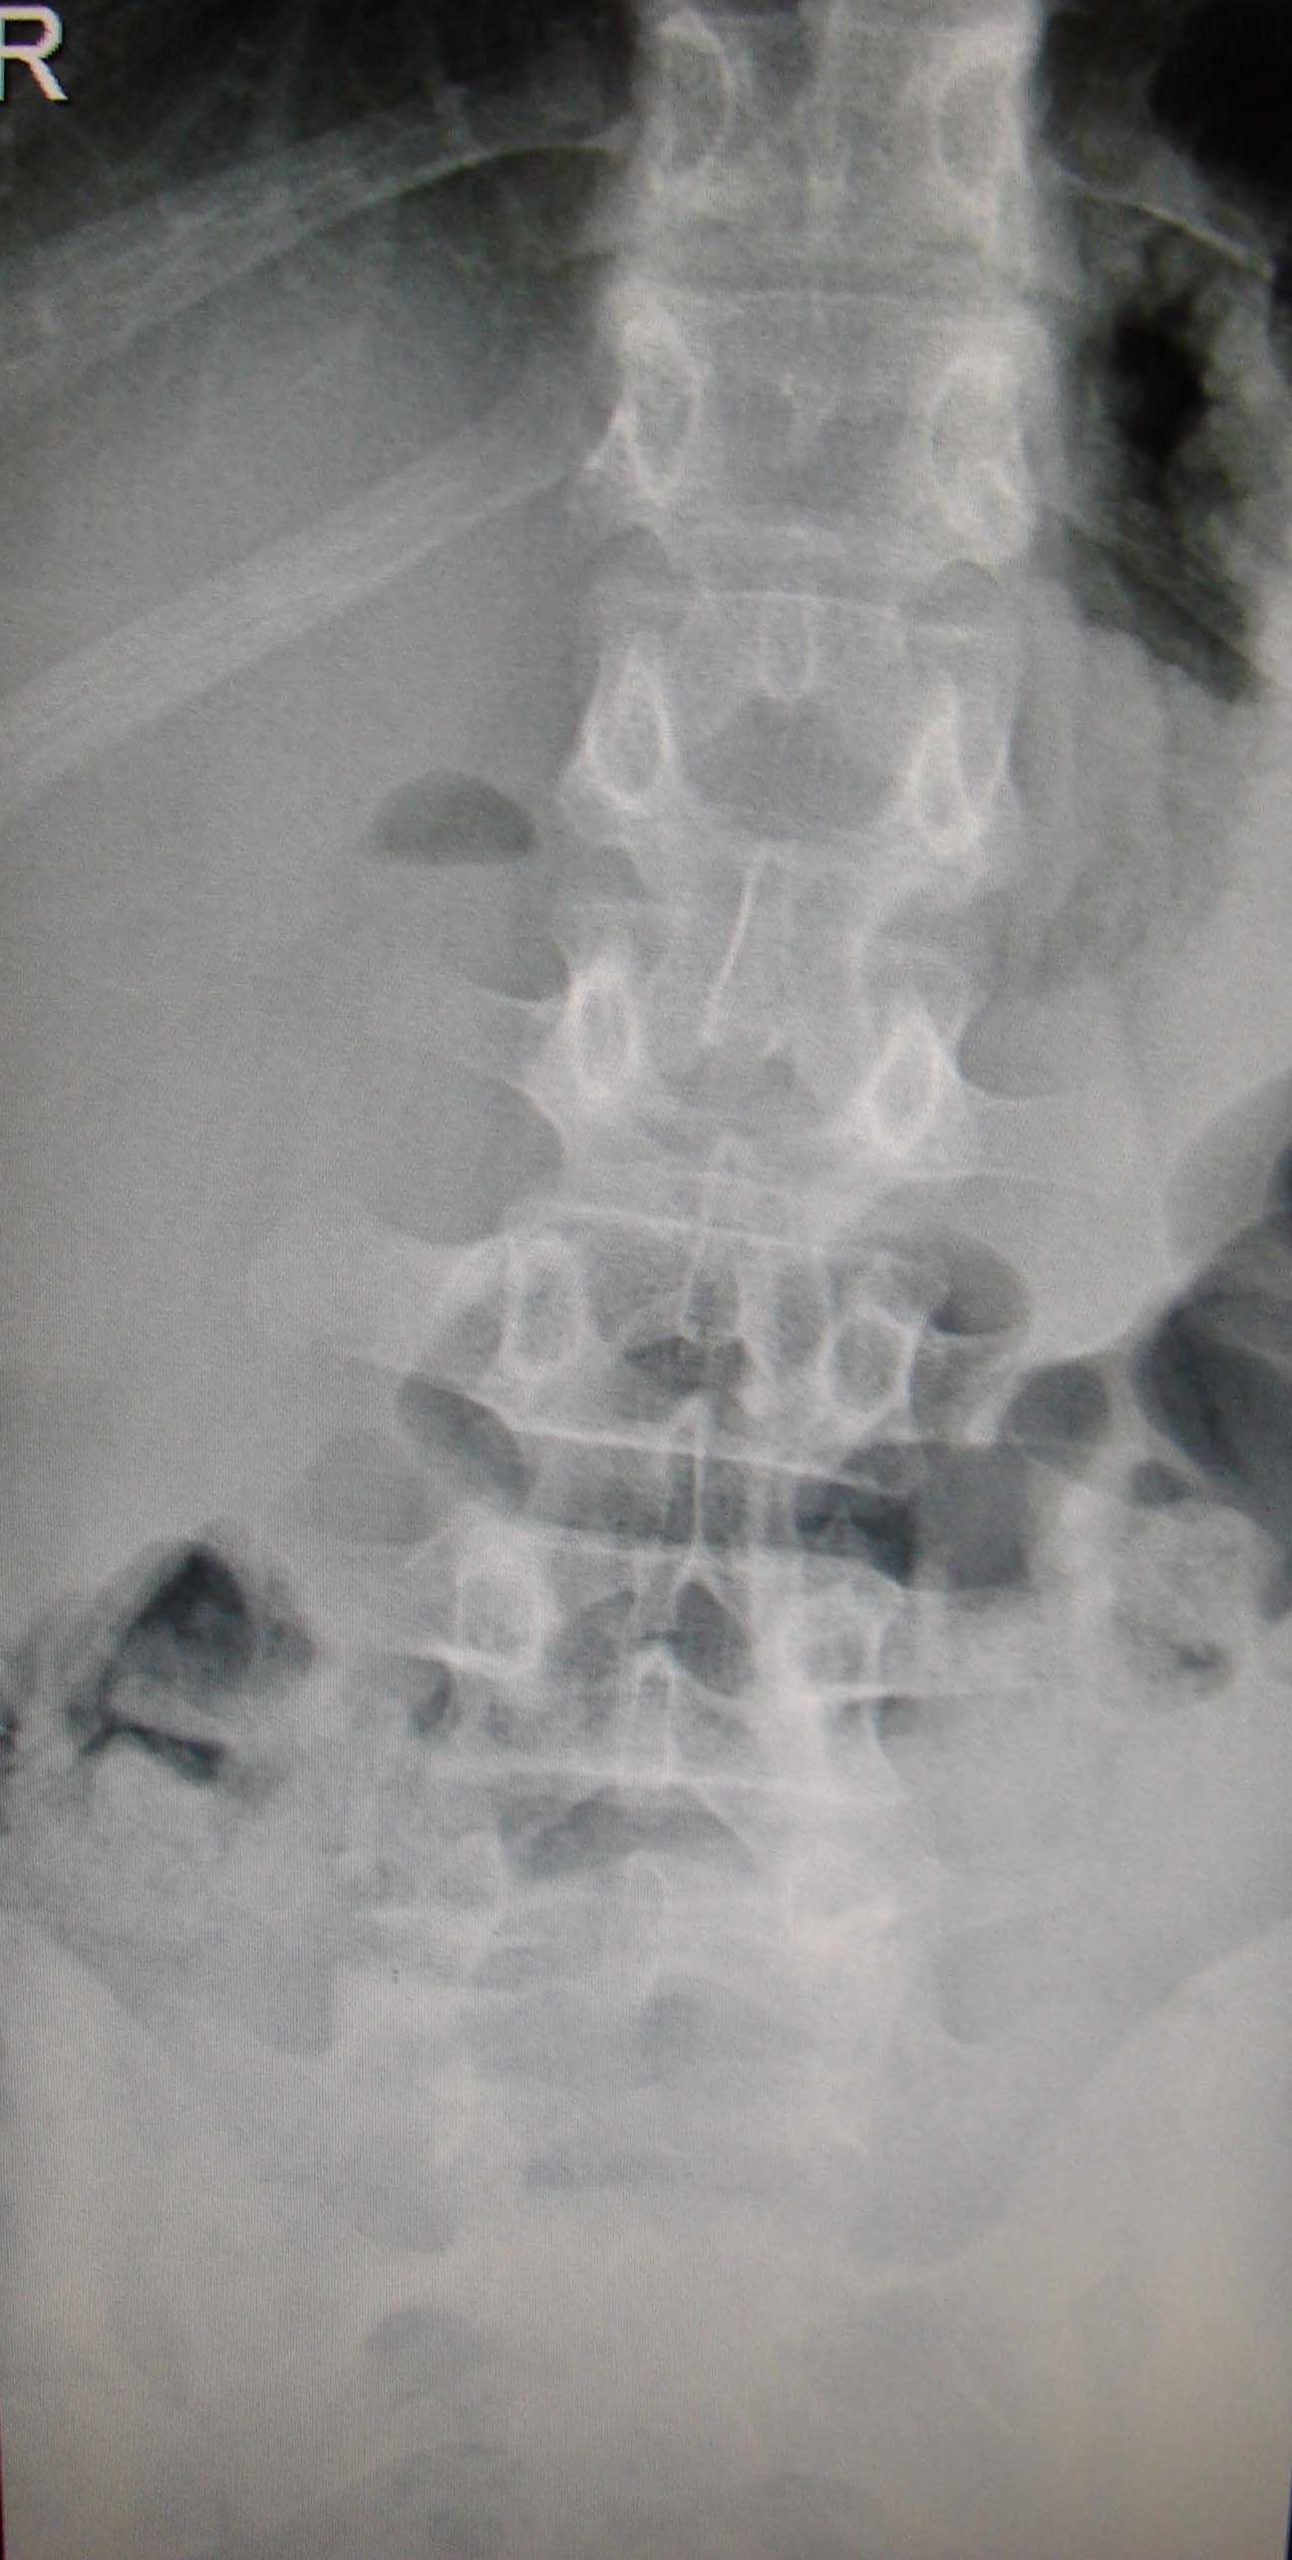

Εικόνα 7 α, β Ακτινογραφίες ΟΜΣΣ δύο χρόνια μετά τη χειρουργική επέμβαση. Παρατηρείται η καλή στήριξη της Σπονδυλικής Στήλης και η ακεραιότητα των υλικών σπονδυλοδεσίας.

Δυόμιση περίπου χρόνια μετά την επέμβαση, η λειτουργική κατάσταση του χειρουργηθέντος ήταν εξαιρετική, συμμετείχε δε σε αθλητικές δραστηριότητες. Αποφασίσθηκε τότε να γίνει αφαίρεση των υλικών σπονδυλοδεσίας.

- α

- β

Εικόνα 8 α, β Προσθιοπισθία και πλαγία ακτινογραφία της ΟΜΣΣ δυόμιση περίπου χρόνια μετά τη χειρουργική επέμβαση. Παρατηρείται η ακεραιότητα των σπονδυλικών στοιχείων και των υλικών σπονδυλοδεσίας.